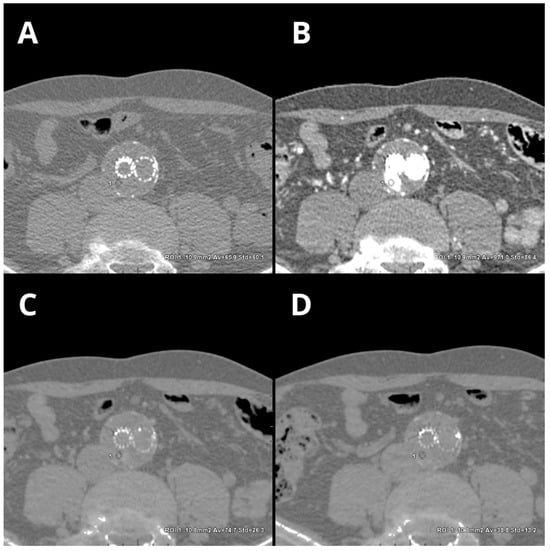

- Boos, J.; Fang, J.; Heidinger, B.H.; Raptopoulos, V.; Brook, O.R. Dual energy CT angiography: Pros and cons of dual-energy metal artifact reduction algorithm in patients after endovascular aortic repair. Abdom. Radiol. 2017, 42, 749–758. [Google Scholar] [CrossRef]

- Kazimierczak, W.; Nowak, E.; Kazimierczak, N.; Jankowski, T.; Jankowska, A.; Serafin, Z. The value of metal artifact reduction and iterative algorithms in dual energy CT angiography in patients after complex endovascular aortic aneurysm repair. Heliyon 2023, 9, e20700. [Google Scholar] [CrossRef]

- Ragusi, M.A.A.D.; van der Meer, R.W.; Joemai, R.M.S.; van Schaik, J.; van Rijswijk, C.S.P. Evaluation of CT Angiography Image Quality Acquired with Single-Energy Metal Artifact Reduction (SEMAR) Algorithm in Patients after Complex Endovascular Aortic Repair. Cardiovasc. Interv. Radiol 2018, 41, 323–329. [Google Scholar] [CrossRef] [PubMed]